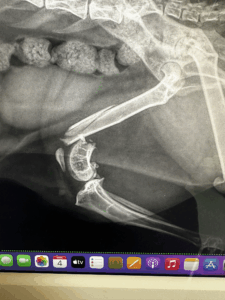

【写真:吸収病巣の歯のレントゲン画像】

こちらは猫ちゃんの吸収病巣のレントゲン画像です。

一見、表面はきれいに見えても、レントゲンで見ると歯の根がぼろぼろに溶けているのがわかります。